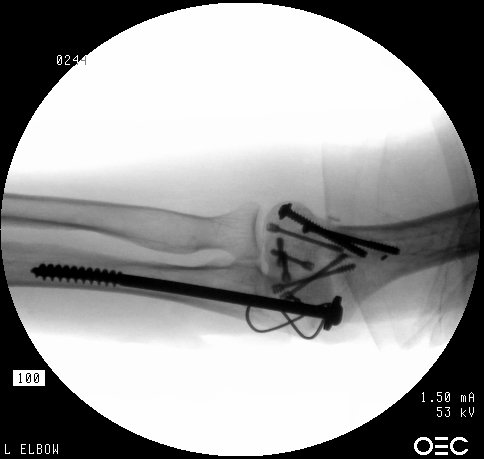

In similar steps, the reconstructed central articular component was secured to the proximal humerus with pins. Once satisfactory reduction was obtained (not yet, as seen here...), the pins were replaced by more Herbert screws. This allowed fixation of the purely osteochondral segments without prominent harware.

Screws were secured from the central articular component to the more proximal humeral cortices.

These provided biplanar fixation, eventually with two screws in each direction.

The lateral column was then secured with two cannulated screws.

The olecranon osteotomy was closed with a 6.5 mm lag screw and (belt and suspenders) tension band technique.